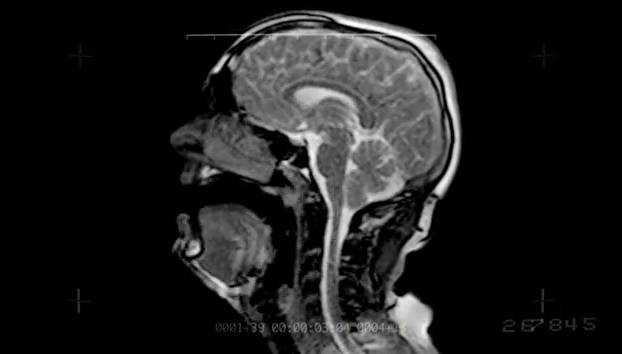

We see that in the first image, to the left side of the brain, there is a tumor formation, whereas in the second image, there is no such formation. Responsible for super encoiding magnet; This section of the website will explain large and minute details of coronal brain cross sectional anatomy.

Mri (magnetic resonance imaging) is a noninvasive diagnostic test that takes detailed images of the soft tissues of the body. Researchers report ultraprecise imaging of a postmortem human brain. Rf = radio frequency coil gradient coil;; Magnetic resonance imaging (mri) is a topic that is delivered in a variety of.